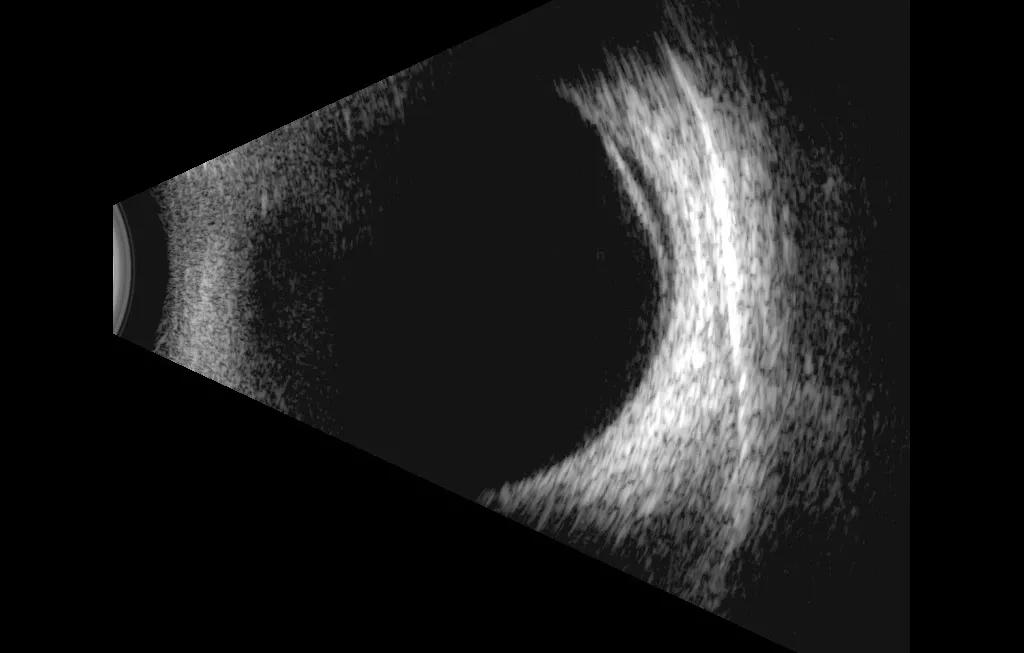

半个月后,小赛的左眼眼前出现固定黑影,发现异常的她请假来到浙江医院三墩院区眼科门诊, 浙江医院眼科洪明胜医师 简单了解病情后,通过眼部超声、欧堡广角彩照、裂隙灯下前置镜等检查,发现小赛左眼的视网膜周边2点钟方位有一个直径大小1mm的 视网膜裂孔,裂孔区视网膜浅脱离范围达到一个象限区域,急需手术治疗。

△(左图)眼部超声提示:左眼视网膜脱离;(右图)欧宝广角彩照检查:可以直观看到(右上角)颞上方视网膜脱离区域以及周边视网膜裂孔区。